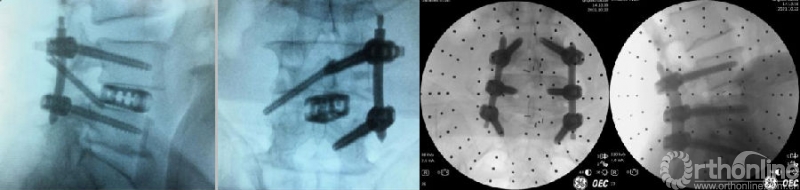

(11)经皮椎弓根螺钉内固定

根据手术需要决定采用何种内固定方式及顺序。常规是双侧经皮螺钉置入,也可选择减压侧两枚经皮螺钉+对侧棘突椎板关节突复合体螺钉的3钉设计,均能符合生物力学要求。减压侧两枚经皮螺钉单边固定,或者单枚棘突椎板关节突复合体螺钉,适应证非常窄,选择需慎重。传统方法均是在C臂透视辅助下,置入螺钉,有条件的医院可以借助骨科手术机器人或导航等辅助置钉。放入合适长度固定棒,锁紧螺钉,去除钉尾。个别情况下,需要先放置对侧椎弓根螺钉并撑开椎间隙后暂时固定,再行同侧减压和椎间隙置入。